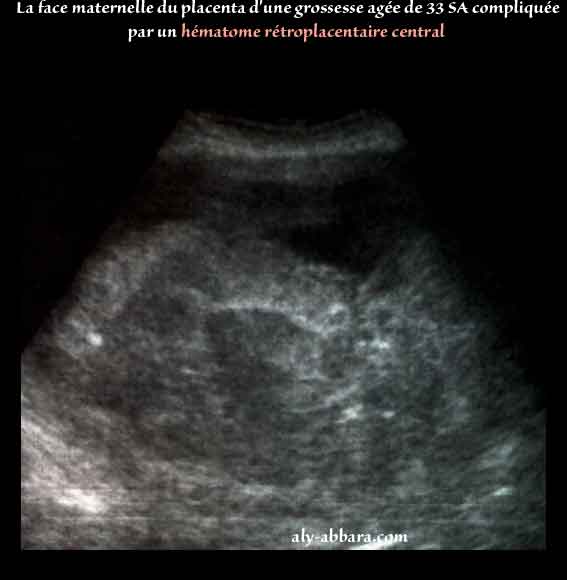

Hématome rétroplacentaire décidual basal central et massif

• Images échographiques et macroscopiques du placenta d'une grossesse âgée de 33 SA, mettant en évidence un décollement précoce du placenta normalement inséré avec la formation d'un hématome rétroplacentaire décidual basal central et massif.

• L'image échographique montre l'étendue et le volume de l'hématome rétroplacentaire.

• Les images macroscopiques permettent de constater que le décollement de la face maternelle du placenta est effectivement central car les bords de ce dernier sont épargnés ; puis sur l'image on peut voir la profonde et large cupule qui n'est que l'empreinte laissée par l'hématome sur le placenta par pression. La superficie du décollement placentaire est évaluée à environ 55 % de superficie de la face maternelle du placenta.

Le poids du placenta est égale à 530 grammes, et l'hématome pèse 500 grammes.

Ce décollement placentaire prématué est survenu dans un contexte d'hypertension artérielle chronique compliquée par une pré-éclampsie sévère (TA à 180 -220/100-120 mmHg), avec une hyperprotéinurie massive (12,4 grammes/litre) ; pas signes biologiques évoquant le diagnostic CIVD ou de HELLP-syndrome associés.

• Cliniquement la patiente se présente aux urgences pour douleurs abdomino-pelviennes s'aggravant depuis quelques jours ; l'examen met en évidence la présence d'une importante hypertonie utérine sans aucun relâchement du muscule utérin ; une hauteur utérine égale à (38 cm à 33 SA) ; col utérin fermé ; aucune métrorragie. Enfin l'échographie permet de constater la présence de la mort fœtale in utero et le présent hématome rétroplacentaire.